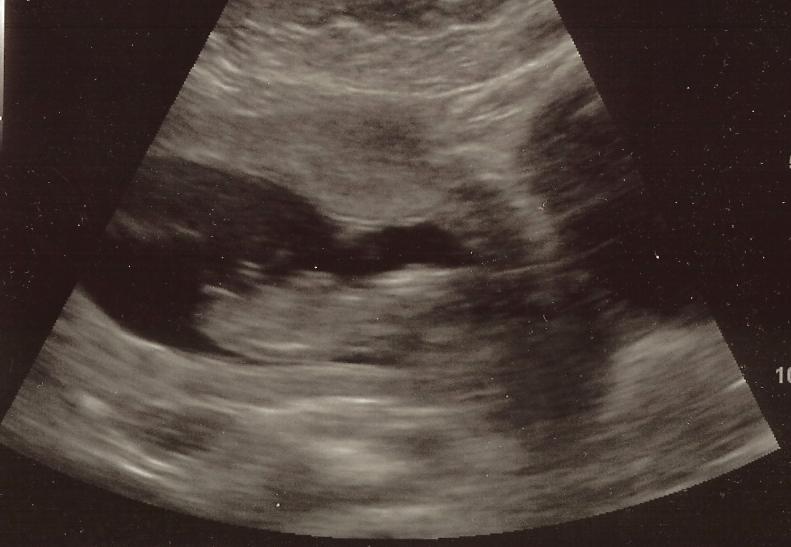

I'm around 12-13 weeks. Thanks!

Number 3 does look flat but it is also sticking out pretty far. 50/50 for me!

Hmmm... a bit tricky, but thinking boy.

I am leaning pink.